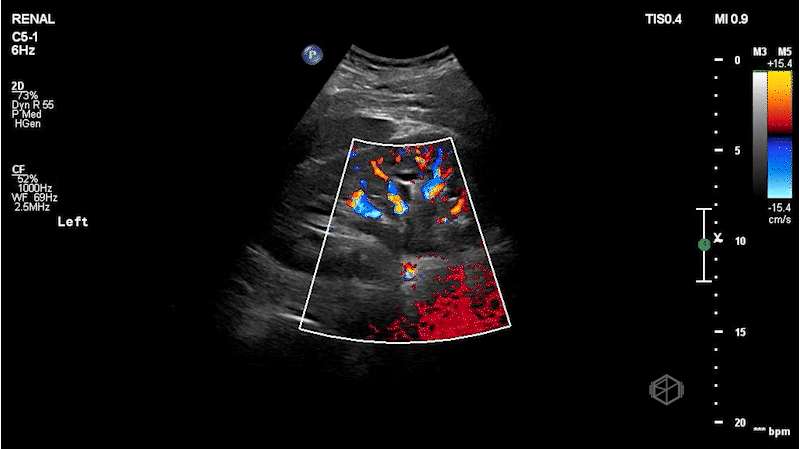

As you know, during the holidays, delivery drivers work extremely hard to get our packages to us as quickly as possible. Dr. Mendelow scanned a middle-aged delivery man with left flank pain that came on suddenly while he was out delivering holiday packages. The right kidney was normal. He obtained the following images:

This patient has mild-to-moderate left hydronephrosis with an approximately 5mm ureteropelvic junction (UPJ) stone. Note the hyperechoic stone with shadowing posterior to it just outside the kidney in image 4 and in clip 2. The patient later had a CT that demonstrated the same but the stone had moved just slightly lower into the proximal ureter.

Diagnosis: Left mild-to-moderate hydronephrosis with a UPJ stone

• It is important to when hydronephrosis is noted to look at the ureteropelvic junction, as subtle stones may be missed. Especially if the bladder scan does not demonstrate any hyperechoic stones or “twinkling” artifact.